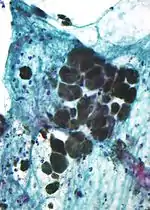

A síntese de melanina é teoricamente explicada pela presença de uma enzima - tirosinase - concentrada no aparelho de Golgi dos melanócitos. O pigmento é originado a partir da polimerização do aminoácido tirosina por intermédio da ação da tirosinase, a qual passa de aminoácido incolor a um pigmento castanho. A tirosina polimerizada deposita-se em vesículas denominadas melanossomas, as quais se deslocam pelos prolongamentos citoplasmáticos dos melanócitos, sendo transferidos para os queratinócitos através de um processo de secreção, denominado secreção citócrina (de célula para célula) Embora exista uma corrente que não concorda com esse processo e sim que os grãos de melanina saem dos melanócitos por , são depositados no liquido intersticial e capturados por receptores na membrana dos queratinócitos, isso explica a ação do sistema imune ao destruir a melanina no caso do Vitiligo é o que prova pesquisas da Associação Fluido Vital. Os grânulos de melanina permanecem no citoplasma dos queratinócitos e se depositam ao redor do núcleo onde realiza a proteção gênica dos mesmos.

Existem duas classes principais de melanina: eumelanina, de cor acastanhada ou preta, e feomelanina, de cor avermelhada ou amarelada. Os grânulos de melanina se dispõem sobre o núcleo do queratinócito, de modo a impedir lesões no DNA da célula pelos raios ultravioleta. A eumelanina é muito mais eficiente que a feomelanina nessa proteção, e por isso os cânceres de pele são mais comuns em pessoas de pele clara, cujo conteúdo relativo de eumelanina é pequeno.